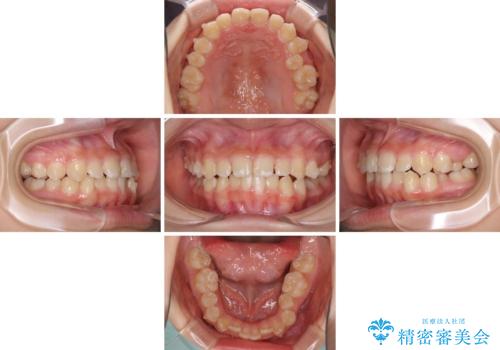

上下の骨幅を改善したことで、スムーズに歯列矯正を行うことができました。

インビザライン治療開始直後に遠方に引っ越しをされたため、通院間隔が長くなり、治療期間が長くなりましたが、しっかりと治療を行うことができました。